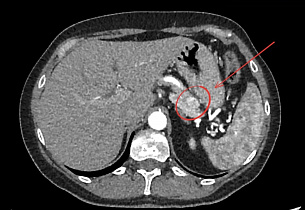

Выполнение КТ или МРТ с контрастированием помогает выявить инсулиному в поджелудочной железе и точно определить ее местоположение. Однако, в некоторых случаях обнаружение инсулиномы на КТ или МРТ может быть затруднительным. Тогда используется эндоультрасонография или эндоскопическое УЗИ.